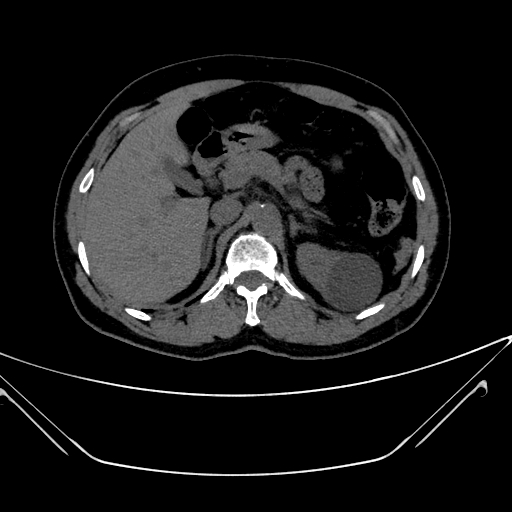

img

Cyst